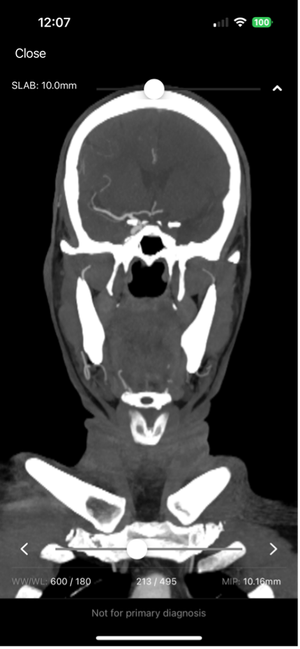

A resident of Larkana Singh until recently was a typical 14-year-old teenage girl in grade 7 who enjoyed listening to Bollywood music and playing with her siblings.

Last month, her world changed. She suddenly developed an intense severe headache, the worst imaginable. Throughout the day, she became tired, lethargic, and couldn’t keep anything down. Her parents, a poor laborer and homemaker, took her to the local district hospital, and a CT scan of the head confirmed bleeding in the brain due to a ruptured brain aneurysm.

We provide devices and treatment of complex brain aneurysms and vascular malformations free of cost. These are some of the complex brain aneurysm we have recently treated in Pakistan. Devices and catheters used for all procedures were provided by Pakistan Stroke Initiative, and in some cases charges for hospitalization as well.